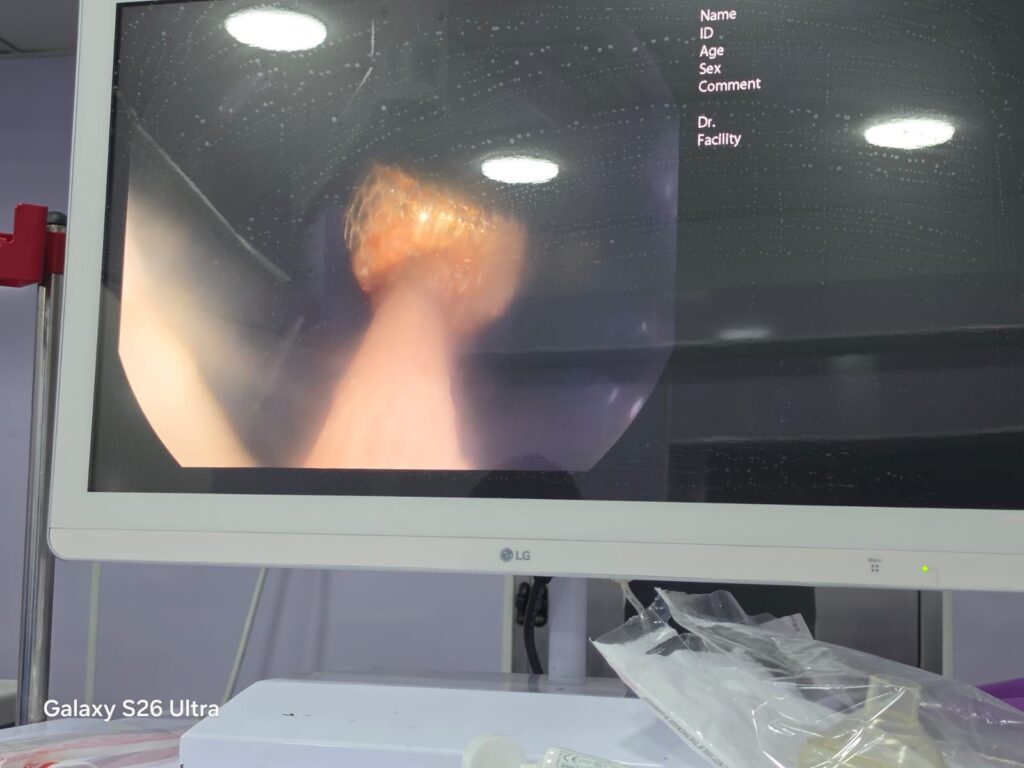

وأشار الأستاذ محمود عبدالفتاح مدير الإعلام والعلاقات العامة بالمديرية، إلى أنه فور استقبال الحالة، تم التنسيق الفوري من خلال مركز الخدمات الطارئة ١٣٧ بالمديرية، وتم تحويل الحالة إلى وحدة مناظير الجهاز الهضمي للأطفال، وإجراء كافة الفحوصات الطبية اللازمة لها، وإجراء منظار عاجل باستخدام التقنيات الحديثة، حيث نجح الفريق الطبي بفضل الله، في استخراج البطارية باستخدام شبكة المنظار، رغم صعوبة الحالة ووجود طعام داخل المعدة، وذلك مع الحفاظ على سلامة الأنسجة وعدم حدوث مضاعفات، وخرجت الطفلة بحالة عامة جيدة، وتحت الملاحظة الطبية للاطمئنان على استقرار حالتها.